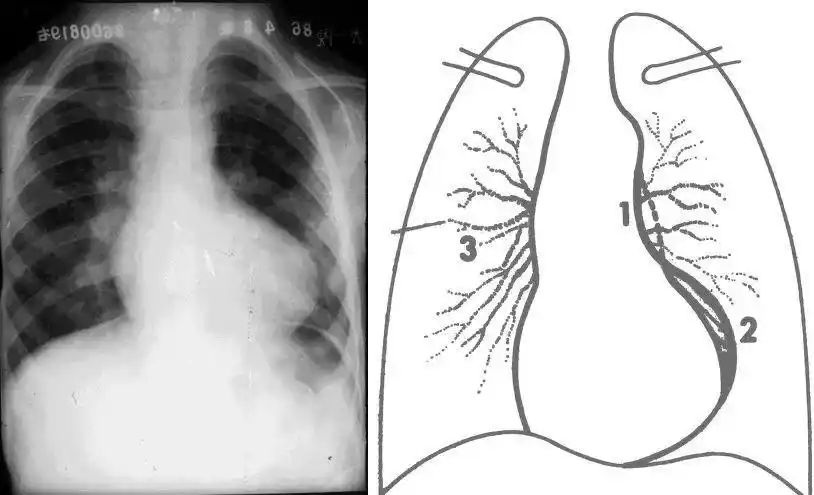

二尖瓣形(或称梨形)心脏增大分型2监护使用生命支持设备及心血管